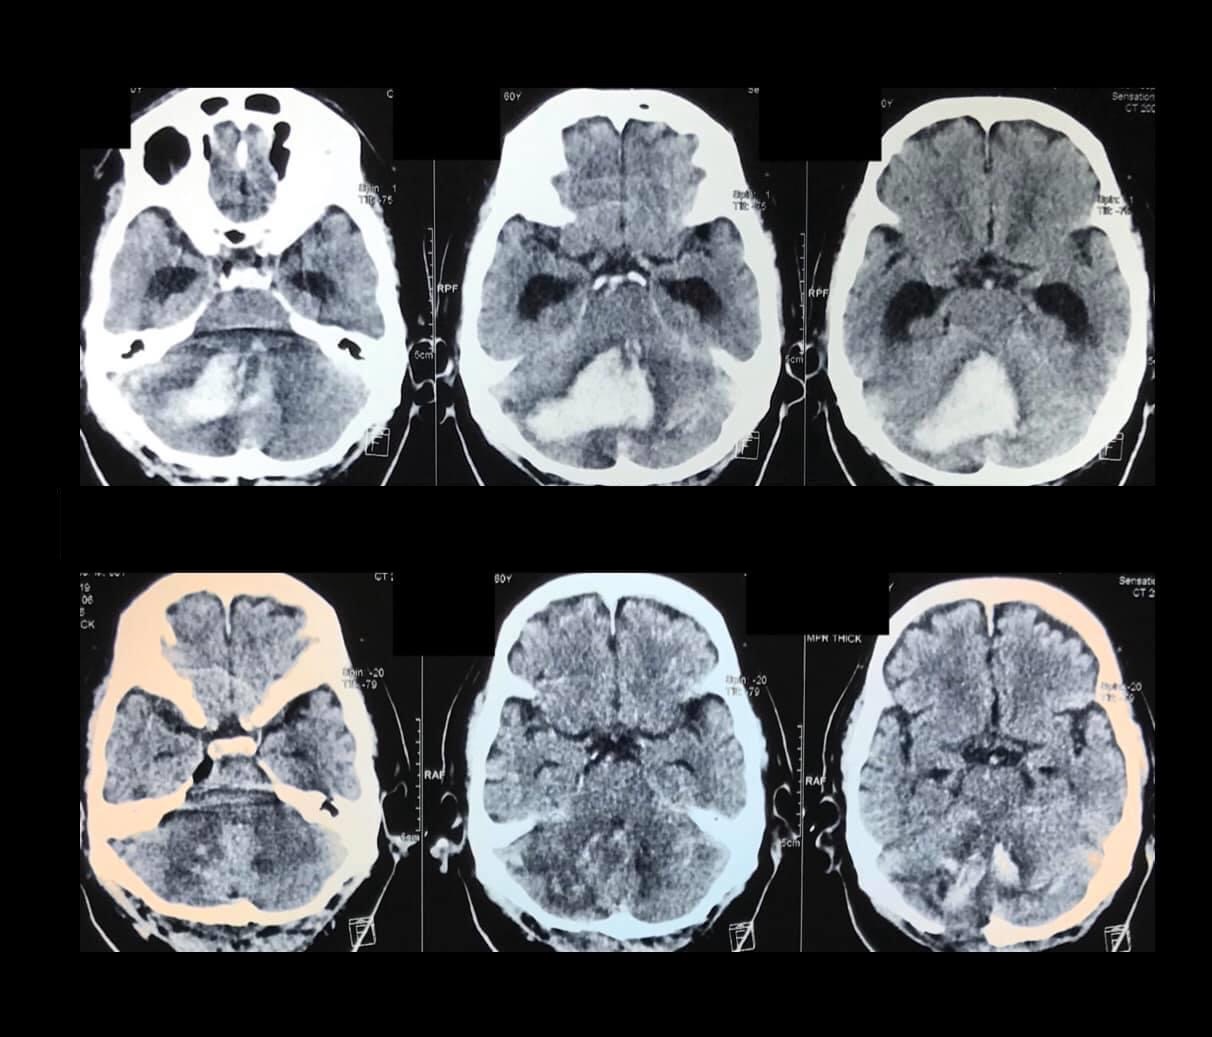

My patient has a blood clot in the brain, does he need a brain operation?

The need for a brain operation would depend on the size and location of the blood clot and the condition (neurologic status) of the patient.

CT scan and/or MRI films or CDs must be brought including pertinent laboratory results/ medical records in order for us to provide you with a sound neurosurgical assessment.